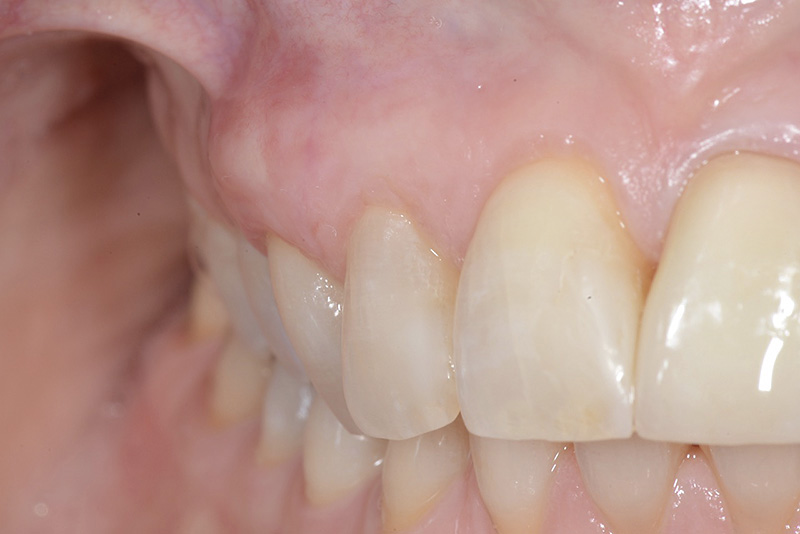

PREMESSA: in seguito all’estrazione dell’incisivo laterale superiore di destra, resasi necessaria per cause batteriche, si decide di affrontare il caso con il posizionamento di un impianto in sostituzione dell’elemento mancante dopo guarigione del sito infetto. Con tecniche rigenerative sia dei tessuti ossei mancanti a causa dell’infezione pregressa, sia dei tessuti gengivali che appaiono inizialmente troppo spostati in alto, si ripristina una corretta morfologia delle parabole (contorni) gengivali e delle papille interdentali (triangoli di gengiva tra due denti vicini).